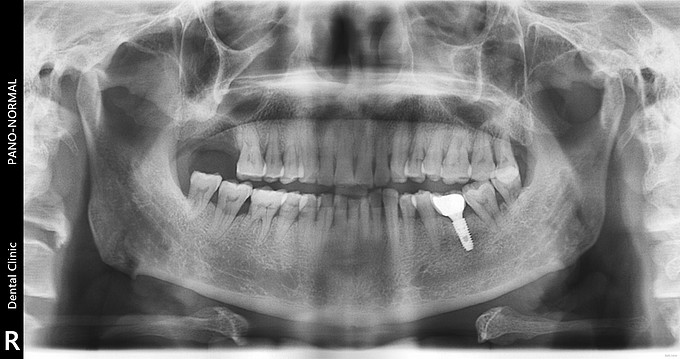

右上后牙缺失种植

右上七牙周炎拔除半年,现种植修复。 缺牙间隙宽 牙槽嵴窄 (牙合)龈距离正常 对合无伸长 邻牙无移位

右上后牙缺失

右上后牙缺失种植修复